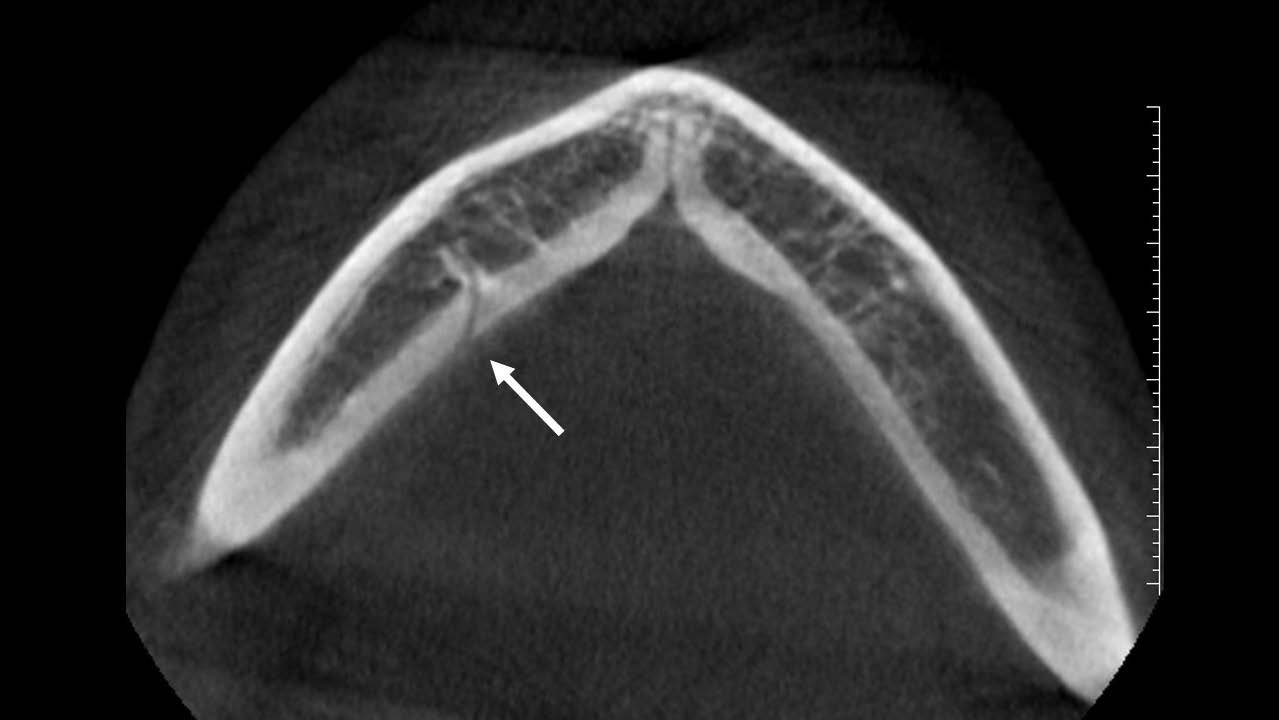

También se pueden encontrar pequeñas foraminas en la superficie lingual de la mandíbula; según su localización éstas se pueden clasificar en foramina lingual medial, si se encuentra en la línea media o cerca a ésta, y foramina lingual lateral (FLL), si se encuentra lateral a la línea media (16, 17). A través de la FFL ingresan ramas de la arteria sublingual, submental (16) y ramas del nervio milohioideo y lingual (18). Su estudio no puede realizarse mediante radiografías, se recomienda usar TCHC y visualizar el FLL en cortes axiales y transaxiales (18) para verificar su comunicación con el CDI (17).

En los trabajos de Wei (16) y Krishnan (17), la variante anatómica que se observó con mayor frecuencia tanto en el lado derecho como izquierdo fue el FLL (figura 3), esto en concordancia con los resultados del presente estudio, lo que se repitió en todos los grupos etáreos. Trost (18) señaló que fueron los varones quienes presentaron mayor número de FLL en comparación a las mujeres, sin embargo, la presente investigación encontró su frecuencia en mayor porcentaje en el sexo femenino, esto podría deberse a que representaban la mayoría de la muestra. Se encontró casos con la presencia de FLL doble, no se ha hallado bibliografía que haga referencia a este tipo de variante anatómica (figura 4).